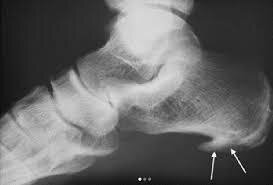

Как обнаружить пяточную шпору?

Провести банальный рентгеновский снимок.

Если ничего не предпринимать, на месте воспаления связка будет понемногу укорачиваться, притягивая фасцию ближе к пяточной кости, а та, не желая расставаться, постепенно формирует костный вырост (остеофит / «шпора») и вот уже вы, прихрамывая, решаете все-таки записаться на прием к врачу.